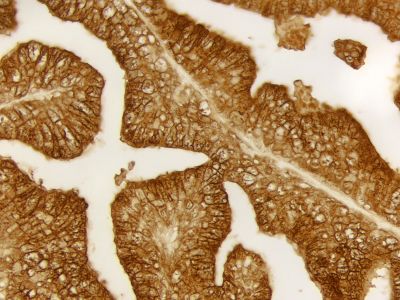

The peroxidase micropolymers of the ImmPRESS HRP polymer reagent limit steric interference and provide enhanced accessibility to the target, avoiding the disadvantages of other polymer systems that use large dextrans or other macromolecules as backbones. The result is crisp, strong staining of antibody targets, especially nuclear and membrane antigens (such as Ki67, estrogen receptor, bcl-2, CD3, CD8 and CD10) and greater sensitivity than other polymer systems.

The staining procedure is simple as shown in the diagram below. Following a blocking step with the diluted normal horse serum, sections are incubated with primary antibody. After a brief wash, the appropriate ImmPRESS Reagent is added to the sections and incubated for 30 minutes. Sections are again rinsed and the slides are developed with the peroxidase substrate of choice.